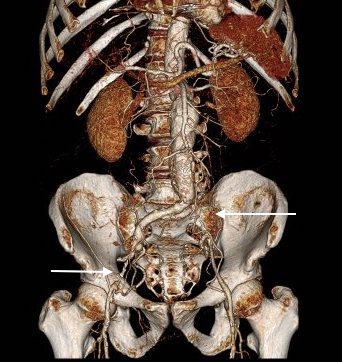

The patient had a 8cm sphere shaped aneurysm arising in the transdiagphragmatic aorta, leaking into the right pleural cavity.

The patient was otherwise a healthy middle aged man with risk factors of smoking and hypertension. The centerline reconstructions showed the thoracic aorta above the aneurysm to be around 20mm in diameter and same below, with the celiac axis and superior mesenteric artery in the potential seal zone of a stent graft. The only plaque seen was around the level of the renal arteries and was focal and calcified. Looking at the list I had made as a comment to the Linked-In post, I realized that I really only had one viable option.

Open repair, usually the most expeditious option, was made challenging by the right hemothorax, making a left thoracotomy hazardous if the lung had to be deflated. Cardiopulmonary bypass would have to be arranged for, and that adds a metabolic hit that greatly raises the stakes. Of the endovascular solutions, the only viable option was TEVAR to exclude the rupture and debranching of the celiac axis and superior mesenteric artery. To those who would advocate for parallel grafts, there was no room in the normal 20mm diameter aorta. And branch systems for rupture are some time in the future. Also, the patient was becoming hypotensive. So the planned operation was first TEVAR to stop the bleeding, and then open surgical debranching. A hybrid repair.